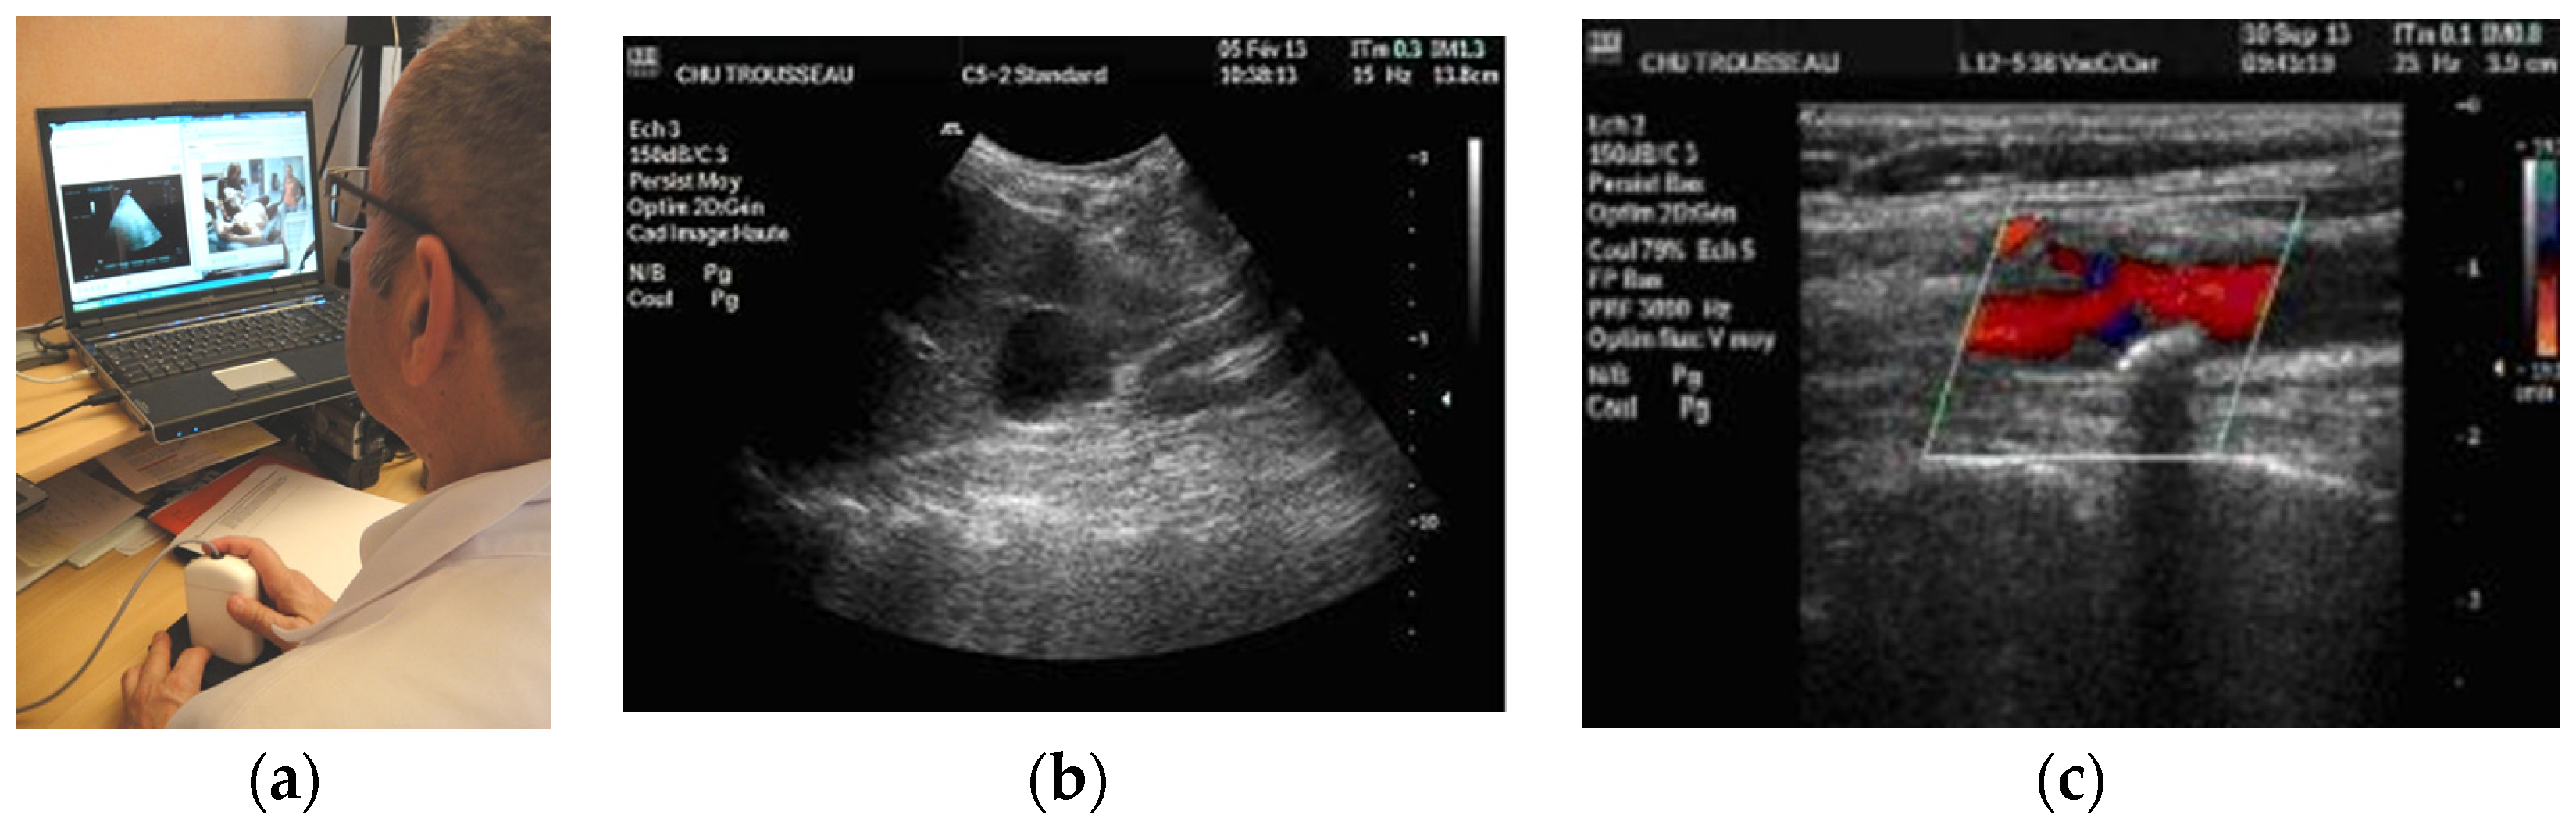

Figure 2. (a) RA expert center computer screen with video of the patient (left) and echographe screen (right); (b) Renal cyst image obtained using RA; (c) Carotid bifurcation with atheromatous plaque in color Doppler using RG.

The three tele-echography methods used included: (a) a teleoperated robotic arm (RA) holding an ultrasound probe; (b) a teleoperated echograph with a motorized probe system (MP); and (c) remote guidance (RG). The RA (Figure 1) system consisted of a large structure that held a standard ultrasound probe. From the expert center (Figure 2), a trained sonographer performed the tele-echography examination by manipulating a dummy probe which teleoperated the robotic arm [1,3]. Throughout the examination, the non-sonographer operator at the patient site was required to position the robotic arm over the patient and to adjust the echograph functions and settings as directed by the trained sonographer. The second system of tele-echography, MP, consisted of a modified commercial echograph with motorized probes [2]. The ultrasound probes used for this system contained internal motors to tilt and rotate the probe transducer which the trained sonographer teleoperated from the expert center (Figure 3 and Figure 4). In addition to controlling the probe orientation, the echograph used for this system was modified to allow for the teleoperation of settings and functions. The final system of remote echography evaluated utilized RG (Figure 5) [5,6,7]. For this system, the non-sonographer (GP) had the probe in hand and performed the echographic examination as directed by a trained sonographer via videoconference.

A summary of the organs examined and the method used for each examination is presented in Table 1. Both the RA and the MP systems provided enough views of the deep organs of interest to deliver diagnoses in 97% of the cases (Figure 2 and Figure 4). For the superficial targets (organs and vessels), MP (Figure 4) and RG (Figure 5) provided the correct view of the organ necessary for the diagnosis in 98% of cases. Overall, tele-echography was not able to return enough information for a safe diagnosis in 11 of the 340 examinations (3.2%). These 11 cases involved imaging of deep organs (gall bladder, spleen, pancreas) on obese patients or patients with very poor echogenicity, and imaging of leg veins (femoral, tibial, gastrocnemius veins) on patients with substantial leg edema. For each of these cases, patients were referred to other medical centers for standard echography examinations.